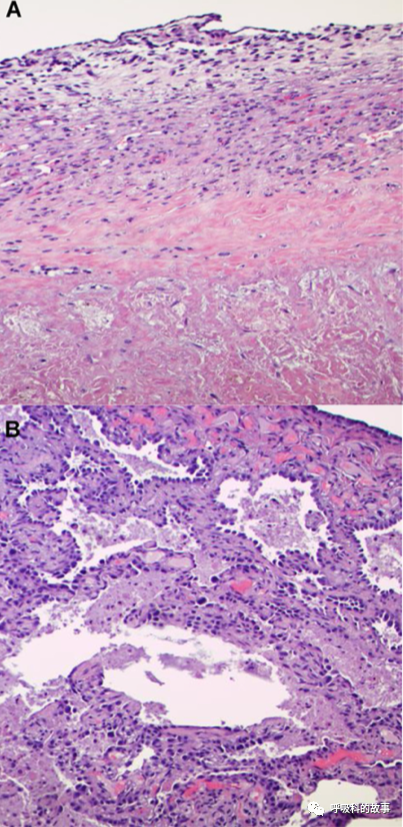

主管醫生再次行支氣管鏡檢查和肺泡灌洗,肺泡灌洗液中沒有嗜酸細胞,這表明嗜酸細胞肺炎或與BAL高嗜酸細胞相關的間質性肺病(結締組織病、藥物性肺炎、肉瘤病或肺朗格漢斯細胞組織細胞病)基本可以排除了。此外,BALF針對感染性疾病和肺癌的檢查也是陰性的。開胸右肺活檢顯示機化性急性肺損傷,伴有機化性纖維素性胸膜炎和斑片狀的肺實質梗塞,伴有大量血管內機化性血栓,沒有惡性腫瘤的證據(圖5)。

這一次氣管鏡進一步行支氣管內超聲掃描,發現隆突下淋巴結腫大,於是進行超聲下淋巴結穿刺活檢,病理顯示大片壞死,沒有肉芽腫性、感染性和惡性細胞的證據。最後,對左下葉的結節進行了穿刺活檢,發現惡性的梭形細胞腫瘤。